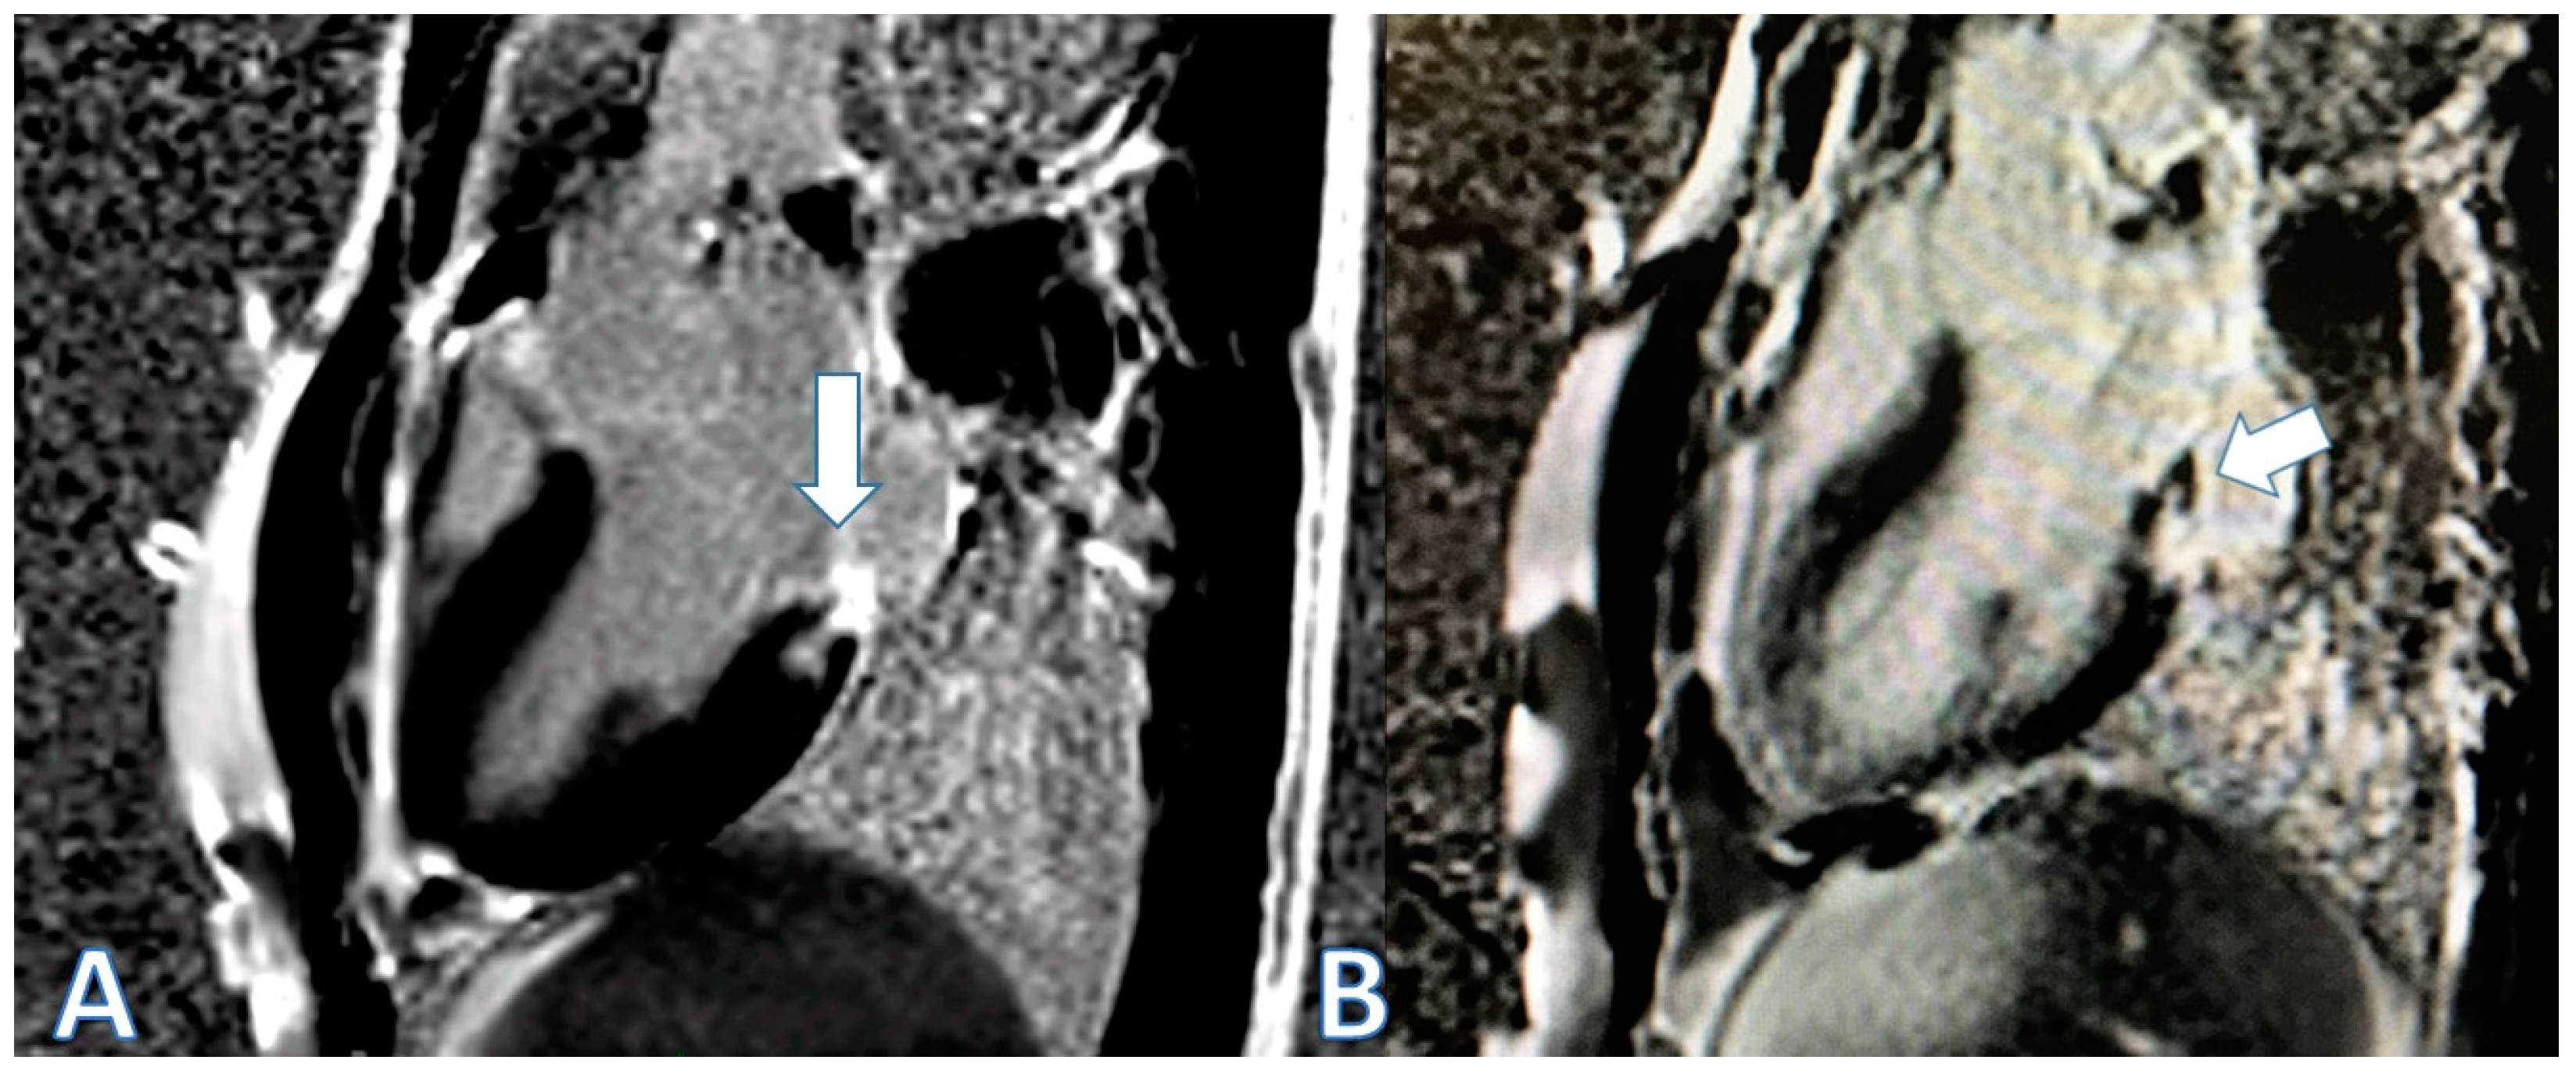

| CMR at hospitalization | LGE of both pericardial leaves and foci of late subepicardial enhancement on the basal inferolateral, lateral, and inferior walls | LGE at the level of the pericardial leaves and a basal inferolateral subepicardial focus | Edema and LGE in the lower-middle, inferolateral, and anterolateral segments | Edema and LGE at the anterolateral, basal-mid inferolateral and basal inferior segments, and intramyocardial in the mid-inferoseptal and apex segments |

| Control CMR at 3 months | Persistence of LGE on the inferolateral wall | Disappearance of LGE | - | - |

| Control CMR at 6–9 months | Persistence of LGE on the inferolateral wall | - | LGE in the inferolateral and anterolateral walls | LGE intramyocardial and subepicardial at inferolateral, anterolateral, and inferoseptal walls (reduced extent) |